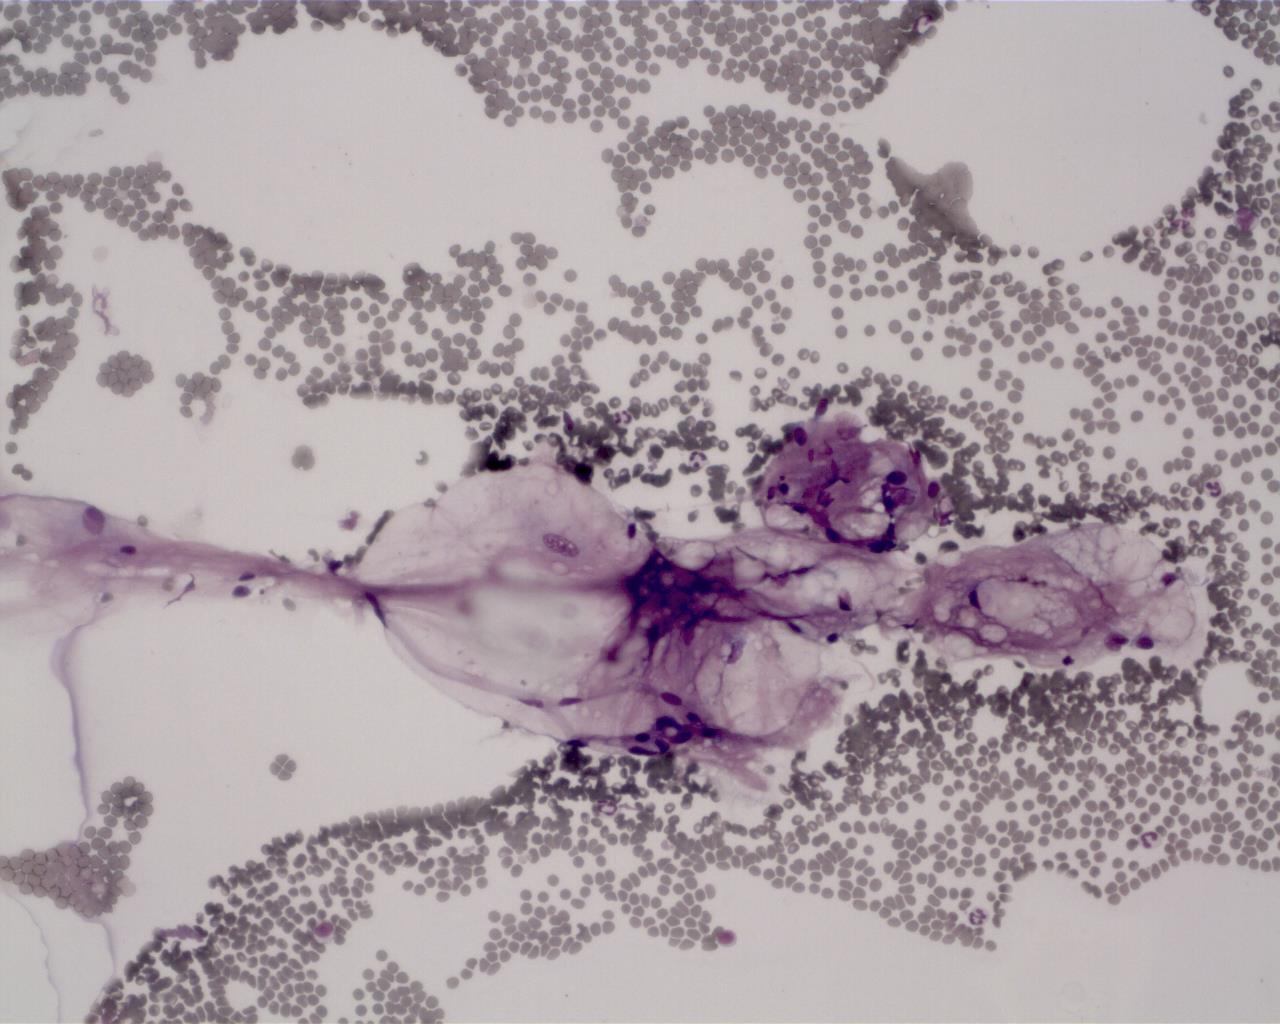

Normal bone marrow 11521041658_5152

골수 / 정상 / 개

Normal canine Sample: bone marrow aspiration(골수흡인표본)